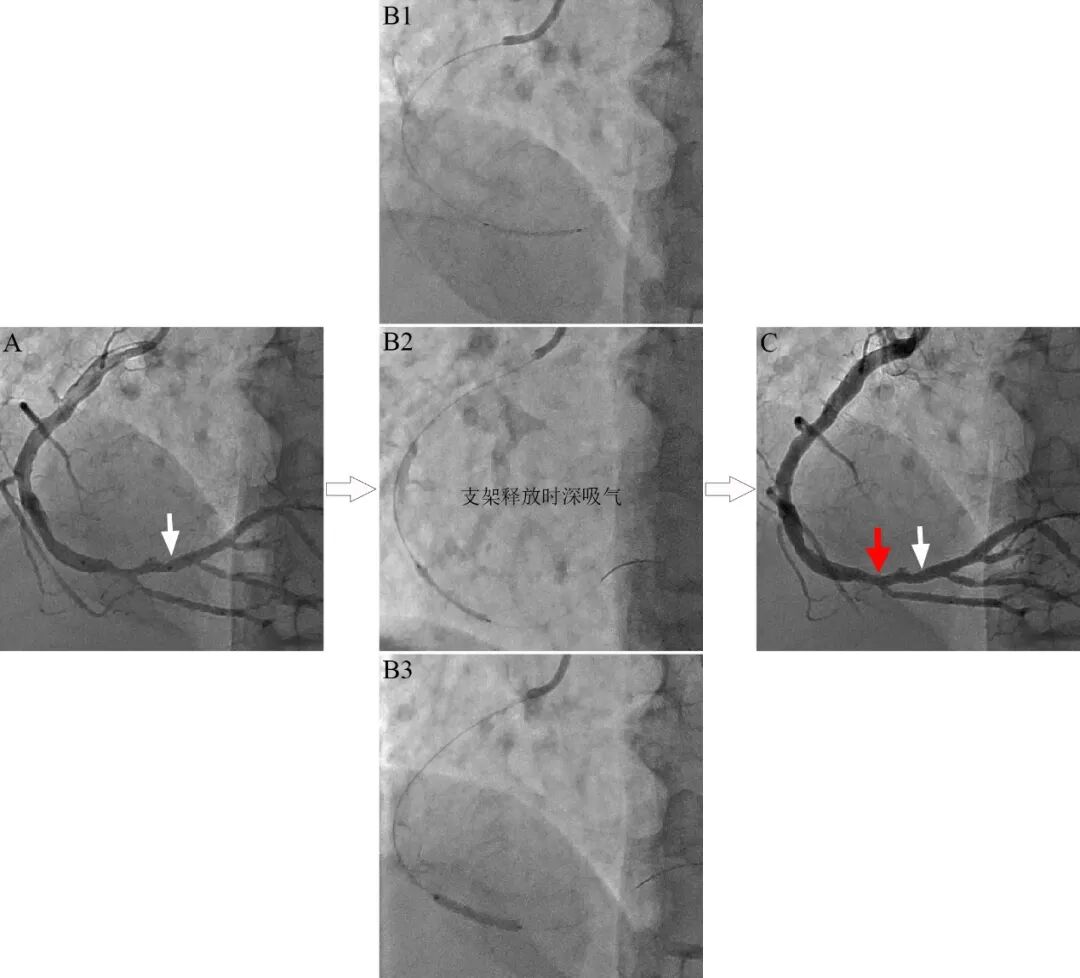

图1 病人深呼吸导致支架意外性移位。右冠远段节段性病变,斑块破裂(A)。支架定位(B1),支架释放瞬间,病人突然深吸气,介入器械(导管、导丝和支架)一起回拉移位(B2),支架释放偏离原先定位处(B3)。复查造影支架移位约10mm,斑块破裂处无支架覆盖(C)。白色箭头为支架远端拟释放位置,红色箭头为支架远端实际释放位置。